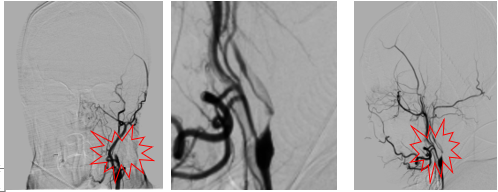

影像诊断

病历夹什么径技·第151期|串联营病历夹:京广连营_https://www.jmylbn.com_新闻资讯_第46张

病历夹什么径技·第151期|串联营病历夹:京广连营_https://www.jmylbn.com_新闻资讯_第47张

病历夹什么径技·第151期|串联营病历夹:京广连营_https://www.jmylbn.com_新闻资讯_第48张

结论:DWI高信号,患者无明显症状(额颞梗死),前交通动脉开放,右侧大脑中动脉显影,考虑右侧颈内动脉慢性闭塞,不除外急性闭塞及急性血栓栓塞。患者于入院后约11小时左右再次出现左侧肢体无力症状,给予静脉替罗非班8ml推注,6ml/小时持续泵入,30分钟症状无缓解。

• 急诊造影发现右侧颈内慢性闭塞,颈内起始部位光滑,基本不见残端。颈内动脉末端有显影,右侧大脑中动脉不显影,考虑病因是右侧颈内动脉慢性闭塞导致血流淤滞进而形成血栓,致使大脑中动脉闭塞。

• 先疏通右侧颈内,放置Carotid Wallstent支架后,输送中间导管和Guiding取大脑中血栓,术后替罗非班持续泵入。